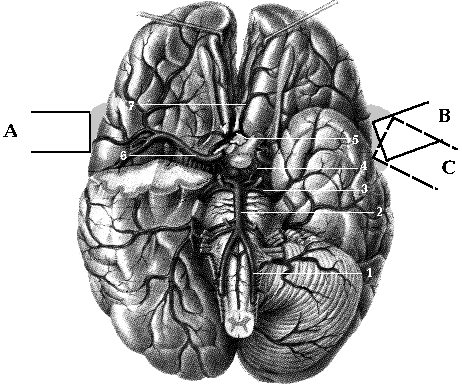

Описаны три основных пути локации внутричерепных артерий (Рис 1.13.):

* Темпоральное окно (исследование СМА, ПМА и артерий виллизиева круга).

* Орбитальное окно (глазничная артерия, сифон внутренней сонной артерии).

* Субокципитальное окно (основная артерия, внутричерепные сегменты позвоночных артерий).

Рис 1.13 Акустические окна для транскраниального исследования. 1- темпоральное, 2- орбитальное, 3- субокципитальное.

Полноценное исследование проводится через все три акустических окна, и позволяет, таким образом, исследовать большую часть внутричерепных артерий.

Рис 1.14. Примерное направление оси ультразвукового датчика при исследовании базальных артерий через темпоральное окно. 1- IV сегмент левой ПА, 2- ОА, 3- ЗМА, 4 - ЗСА, 5- ПСА, 6- СМА, 7- ПМА.